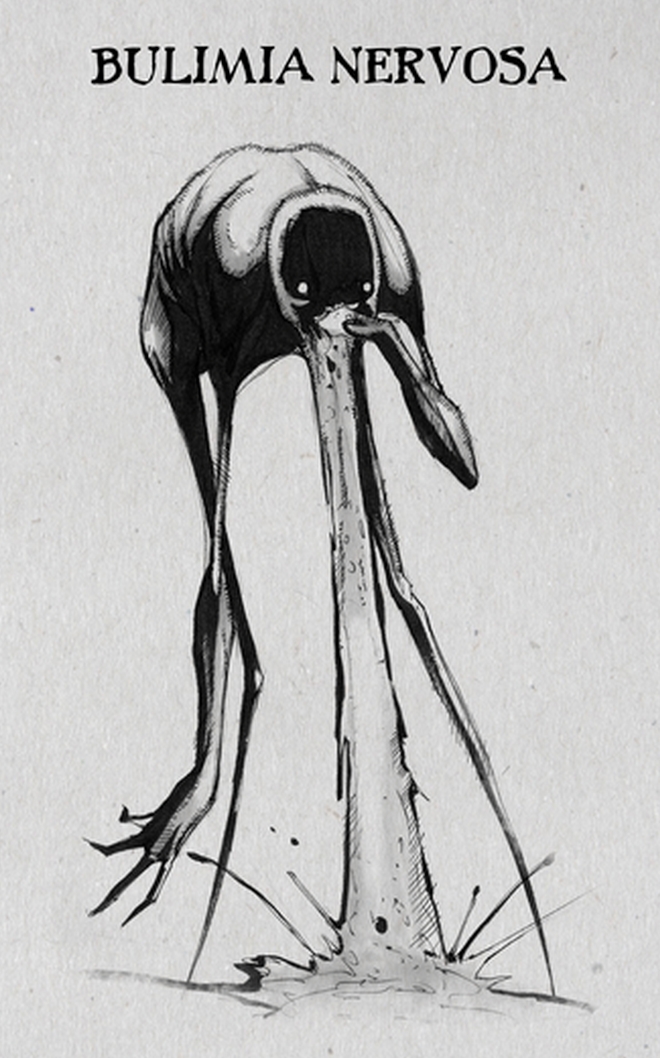

Ο Αμερικανός κομίστας μελέτησε τις ψυχικές ασθένειες και τις διαφορετικές εκφάνσεις τους και αποφάσισε να τις αποτυπώσει με το ιδιαίτερο στιλ του στο χαρτί. Παρουσίασε τις δημιουργίες αυτές στην πρωτοβουλία InkTober τον Οκτώβριο του 2016. Η απόδοσή τους προκάλεσε μεγάλη αίσθηση για τη ρεαλιστικότητά τους και έκαναν μέσω διαδικτύου τον γύρο του κόσμου.

Αξίζει να σημειωθεί ότι στο InkTober οι συμμετέχοντες σχεδιαστές καλούνται κάθε μέρα του μήνα (ή όσες ημέρες δίνουν το παρών) να φιλοτεχνούν από ένα τουλάχιστον σκίτσο με μελάνι. Ο Coss σχεδίασε συνολικά 18 σκίτσα για 18 διαφορετικές ψυχικές διαταραχές.

Βουλιμία